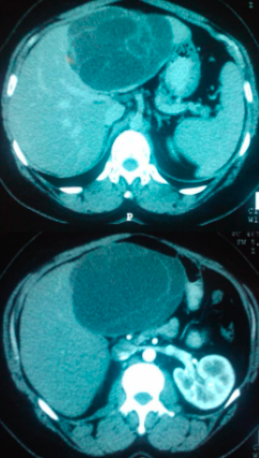

CA de Fígado em Cirróticos

USG + dosagem de alfafetoproteina 6/6 meses

No USG: investigar se nódulo > 1 cm

Fígado